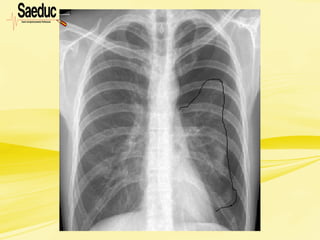

Respiração paradoxal ou

Tórax instável

• Giram em torno de 1,4% nos traumas de

tórax;

• Provocado por fratura de múltiplas

costelas;

• MECANISMO DE TRAUMA: impacto sobre o

esterno (nas colisões frontais, o esterno pára

contra a coluna da direção e a continuação do

movimento da parede torácica posterior para

frente dobra as costelas até estas fraturarem)

ou sobre a face lateral da parede torácica (na

colisão lateral, ocorre impacto na parede lateral

do tórax). Surge quando 2 ou mais costelas

adjacentes são fraturadas em pelo menos 2

lugares.